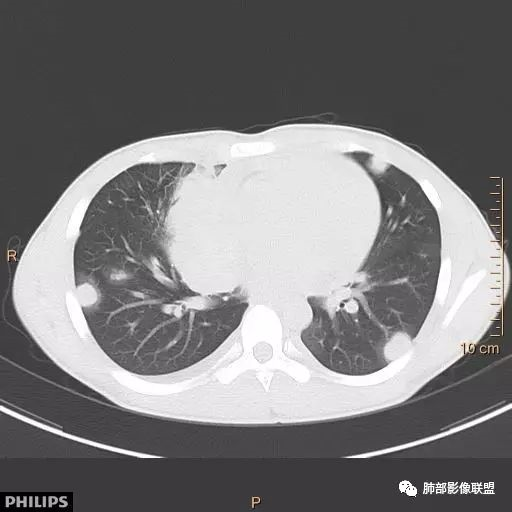

秦化君: 右前上纵隔软组织密度肿块,边缘部分清晰澎隆,与血管及心包间界线不清,密度较均匀。挤压相邻肺组织形成膨胀不良,侵及胸膜形成胸腔积液。双肺内见随机分布结节。考虑纵隔恶性占位(肺及胸膜转移),生殖细胞瘤,畸胎瘤,淋巴瘤。建议穿刺活检。

放射线 (王秀仙): 右侧前纵膈巨大肿块,与纵膈大血管分界不清并受压,右肺组织受压膨胀不全,密度不均,内可见高密度钙化及低密度坏死区,双肺多发结节状转移灶,右侧胸腔积液,年轻男性,考虑生殖细胞肿瘤,精原细胞瘤可能性大。

宇宙: 男性小孩,右前纵膈不规则肿块,与心脏及大血管分界不清,邻近肺组织受压,其内可见钙化及低密度坏死,两肺多发类圆形结节,右侧胸水,考虑精原细胞瘤伴两肺及胸膜转移,鉴别恶性畸胎瘤。

金豆 (刘权威): 病灶主体位于纵隔,密度不均,内可见点状钙化灶,邻近肺组织受限不张,两肺散在结节,右侧胸水,9岁,恶,生殖类,恶性畸胎瘤,鉴别精原。

放射小白: 男9岁,胸痛,定位右前纵隔占位,内部可见钙化灶,右肺局部实变,两肺散在结节灶,右侧胸腔少量积液,常规考虑生殖类肿瘤,精原细胞瘤伴两肺转移,请结合实验室检查。

良孑: 右侧前纵膈巨大肿块,与纵膈大血管分界不清并受压,右肺组织受压膨胀不全,密度不均,内可见高密度钙化及低密度坏死区,坏死边界不清,双肺多发结节状转移灶,右侧胸腔积液,定性恶性,考虑生殖细胞肿瘤,精原细胞瘤或内脏窦瘤可能性大。

位移: 右侧前纵膈巨大肿块,内可见钙化及坏死区,两肺多发结节状转移灶,右侧胸腔积液,儿童,男,考虑生殖细胞肿瘤,精原细胞瘤可能性大,其次恶性畸胎瘤,外周性原始神经外胚层肿瘤。

蔡磊: 男孩,9岁,胸痛10天就诊。前纵隔偏右侧巨大肿块,内见点状钙化,与周围大血管结构不清,推移挤压。右肺受压,节段性不张。增强后双肺内多发类圆形实性结节。恶性病变肺内转移,生殖可能。

右前纵隔巨大软组织肿块,主要偏向右侧生长,边界不清,密度不均匀,内见大片状低密度坏死区及散在钙化灶,未见骨骼影及脂肪密度影。、双肺随机分布的转移瘤结节,右肺肺不张及右侧胸腔积液,提示恶性肿瘤病变伴双肺及胸膜转移。